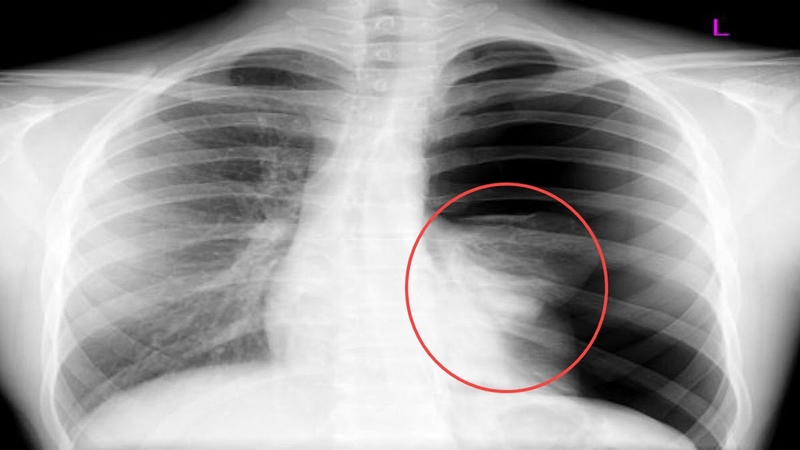

Hình chụp X Quang bệnh nhân bị tràn dịch màng phổiTheo thống kê, ở nước ta nguyên nhân tràn dịch màng phổi thường gặp nhất gồm: